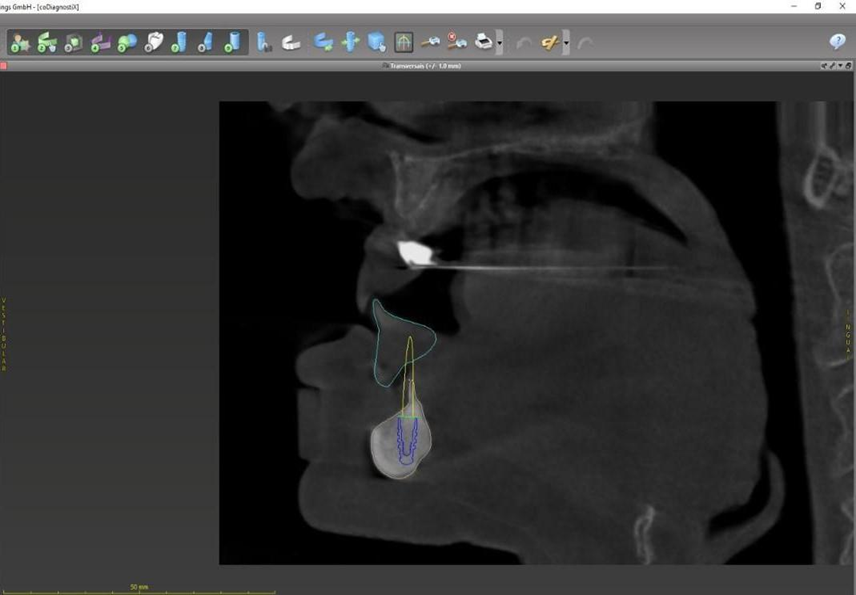

Paciente de 62 anos, do sexo feminino, sem comorbidades e história médica pregressa, apresentava severa reabsorção óssea em regiões anteriores e posteriores da mandíbula devido a uma peri-implantite (Figuras 1A e 1B). Feita a remoção dos implantes, a paciente optou por utilizar uma prótese total mucossuportada até a nova intervenção com prótese do tipo protocolo inferior. Após seis meses, a mandíbula encontrava-se cicatrizada (Figura 2). Como parte do protocolo diagnóstico, foi realizada tomografia computadorizada pela técnica do duplo DICOM. Com a severa perda óssea em região anterior de mandíbula, optamos por realizar a cirurgia de forma guiada, aumentando a previsibilidade e precisão da cirurgia. Os arquivos obtidos foram exportados para o software CoDiagnostiX, possibilitando a realização do planejamento reverso e o subsequente posicionamento virtual dos implantes (Figura 3). Com base no planejamento, optou-se pela instalação de quatro implantes Implacil Osstem CM AR Due Cone (3,5 x 7 mm), associados a mini-cônicos de 1,5 mm (Figuras 4A, 4B, 4C, 4D e 4E). A partir da tomografia da prótese da própria paciente, confeccionaram-se duas guias cirúrgicas: uma guia de pino de fixação (Figura 5) e uma guia de fresagem para a instalação dos implantes (Figura 6). Durante o procedimento cirúrgico, inicialmente foi posicionada a guia de pino de fixação para fresagem dos pinos de fixação e orientação da sequência cirúrgica (Figura 7). Após essa etapa, a guia foi substituída pela guia de fresagem dos implantes (Figura 8), utilizada para a fresagem e inserção dos implantes planejados (Figura 9). Concluída a instalação, optou-se por seguir o fluxo analógico, com a adaptação dos mini-cônicos 1.5 mm (Figura 10), realização da transferência de moldagem com silicona de adição leve e sutura com fio absorvível Vycril 6-0. O guia inicial foi adaptado com broca Maxicut, possibilitando sua utilização como molde de orientação para o laboratório protético (Figura 11). Após a moldagem, foram posicionadas as tampas de proteção sobre os implantes. Na fase protética, transcorridas 48 horas do procedimento cirúrgico, foi realizada a prova clínica da barra metálica e dos dentes (Figura 12). Na etapa subsequente, 72 horas após a cirurgia, procedeu-se à instalação e entrega do protocolo mandibular inferior e radiografia prévia, reabilitando funcional e esteticamente a paciente em curto espaço de tempo (Figuras 13A e 13B).